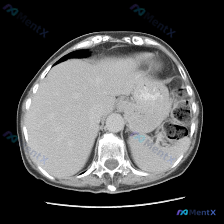

今天看到一份很有意思的腹部CT影像资料,用户一开始提示的是「脾脏病变」,但仔细阅片后发现完全不是这么回事,反而藏着一个要命的急症。整理一下思路和大家分享。 先看影像基础信息 这是一张腹部CT软组织窗横断面图像。 「预设焦点」核查:脾脏到底有没有问题? 既然提示了脾脏,我第一时间先看了脾脏区域: -...